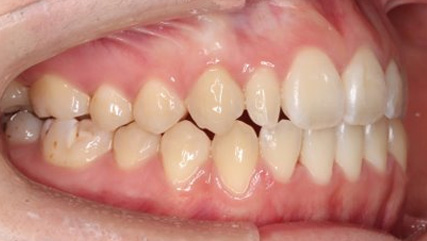

上顎前突といわれ、上顎の前歯が唇側に出ている状態を言います。

前歯が出ることで見た目の問題もありますが、口を閉じることができない、口呼吸をしてしまう、外傷などのリスクがあります。

日本人に叢生の次に多い不正咬合と言われており、自然に治ることはありません。また上の前歯が出ている事だけが気になるかもしれませんが、多くの場合、上顎の奥歯の位置に問題があることが多く、部分矯正でなく根本的な治療をした方がいい場合が殆どです。

口を閉じることができないことで、鼻呼吸でなく口呼吸をしてしまい、結果、成長期の場合顎の骨の成長を邪魔してしまうとも言われております。その他、口呼吸はアトピーなどを含むアレルギー症状の悪化、風邪を含むウイルス性の感染症にかかりやすいなどのリスクも増大してしまいます。

歯並びだけでなく全身への影響も多い為、早期の治療をおすすめ致します。